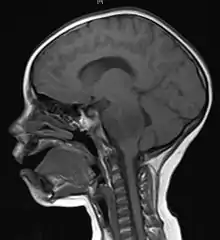

![]() | |

| Brain metastasis in the right cerebral hemisphere from lung cancer, shown on magnetic resonance imaging | |